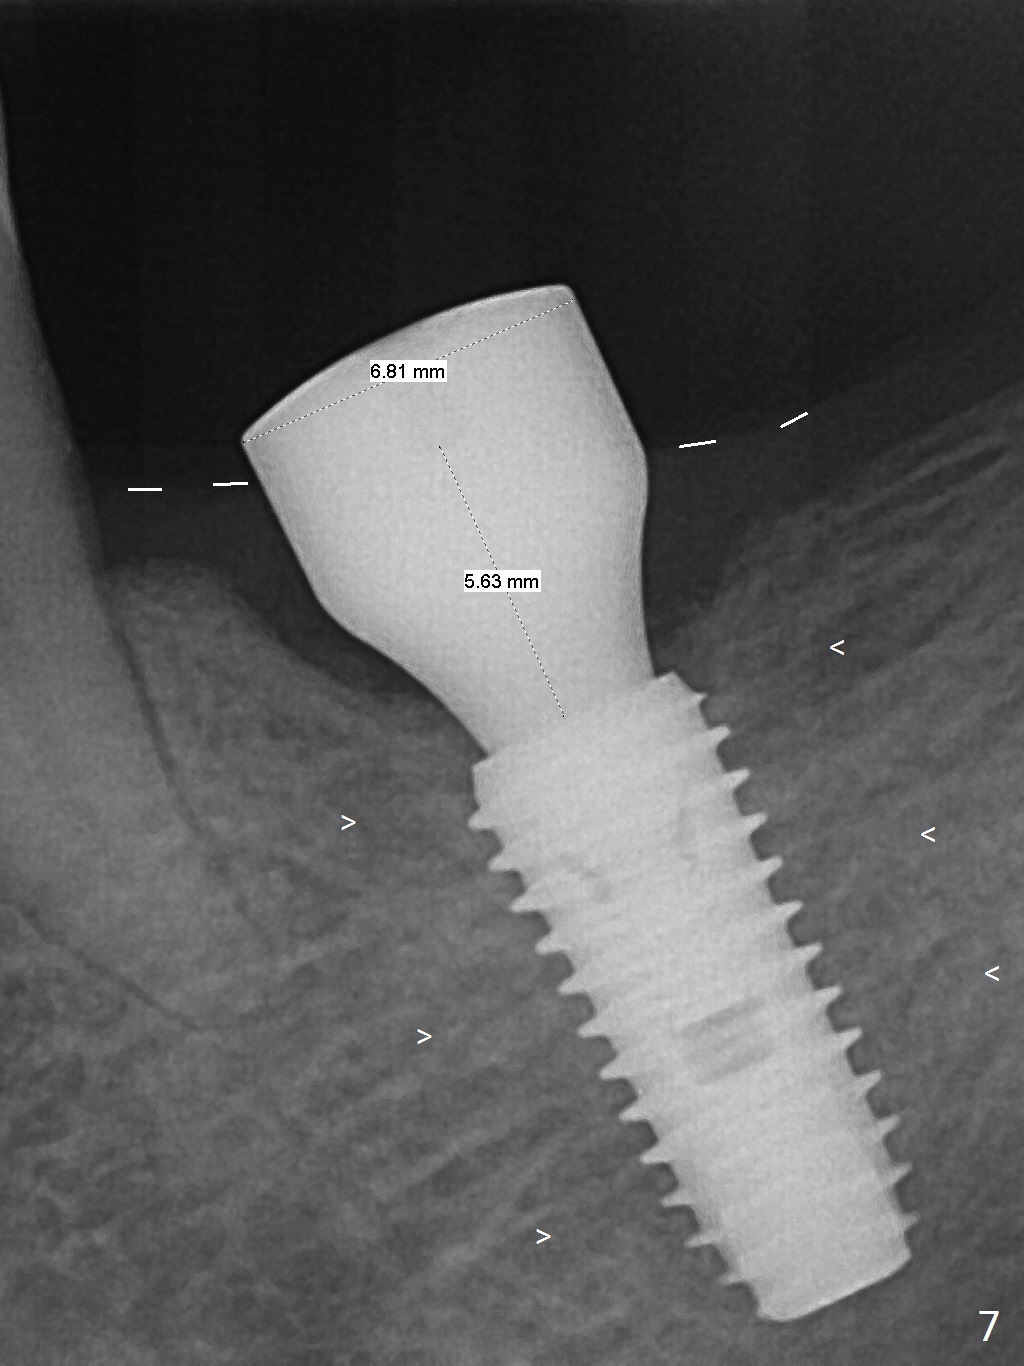

As indicated by CBCT, the ridge at the site of #19 is pointed (Fig.1). After regional ridge reduction (Fig.2) and use of 2 mm pilot drill for 8.5 mm, the depth is actually ~ 10 mm. After sequential osteotomy until 4.3x10 mm drill, the osteotomy is in fact 11.5 mm deep; a 5x11.5 mm implant is placed with <35 Ncm (Fig.3). Panoramic X-ray shows the implant close to the superior border of the Inferior Alveolar Canal (Fig.4 red dashed line). The ridge looks wider and more bulging (*) when a 6.5x5.5(5) mm abutment, allograft/Osteogen and Osteotape (GBR) are placed (Fig.5 (lingual) and 6 (buccal)). Periodontal dressing is then applied. There is no postop paresthesia. The abutment dislodges 3 weeks postop. A healing abutment is placed (6.5x4 mm). The patient returns for restoration 4 months postop; bone density appears to increase around the implant (Fig.7 arrowheads). When a 7.5x5(4) mm abutment is placed, there is transient pressure on the gingiva (blanching). The mesial gingival trough is formed by Diode laser prior to impression.